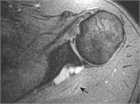

1. 肩関節の痛みの原因として、腱板断裂、石灰性腱炎、凍結肩(五十肩、肩関節周囲炎)、変形性関節症を想起すべきである(推奨度1)

1. 肩の痛みを訴える患者で、①棘上筋の筋力低下、②外旋筋の筋力低下、③インピンジメント徴候、の3つがそろっていれば98%の確率で腱板断裂と診断できる(推奨度2)